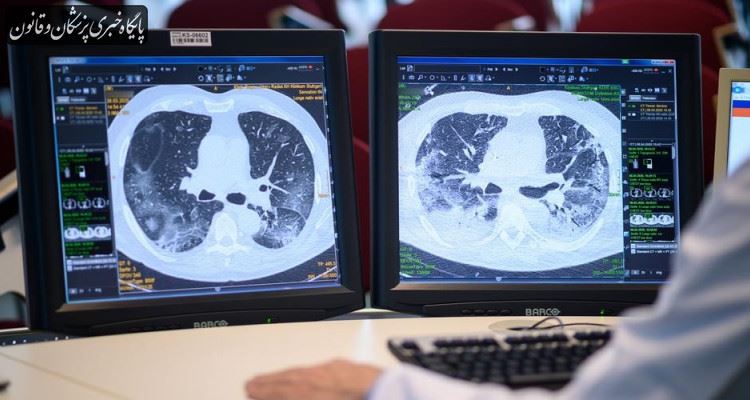

رمضانی درگیری ریه را مهمترین و دردسرسازترین درگیری ارگانهای بدن با کرونا دانست و گفت: در این شرایط اصل دردسر ایجاد میشود که بیماران را بدحال میکند. از ورود ویروس تا شروع علائم ممکن است چند ساعت تا ۲ هفته زمان بگذرد که در مورد سایر ویروسها این طیف زمانی به این وسعت نیست و این درحالی است که برخی افراد در مواجهه با کرونا هیچ علائمی پیدا نمیکنند و تا آخرین روزهای بیماری بدون علائم میمانند، درحالی که امکان انتقال بیماری به سایرین را دارند و ویروس در بینی و مخاط دهانشان ترشح میشود.